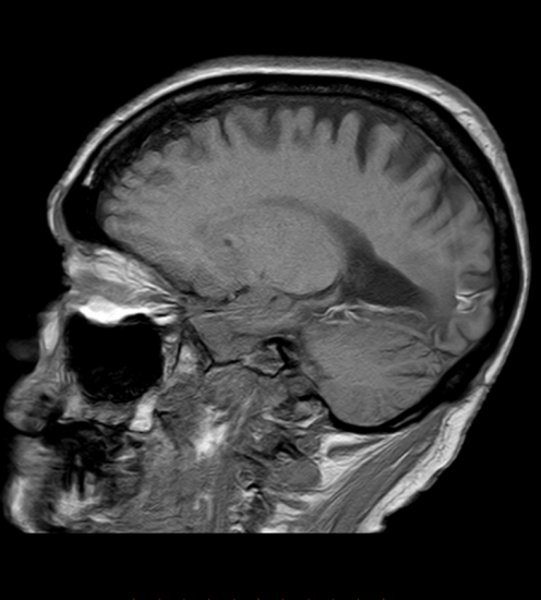

Posteriorinfarkt

Posteriorinfarkt T1 mit KM - sagittal